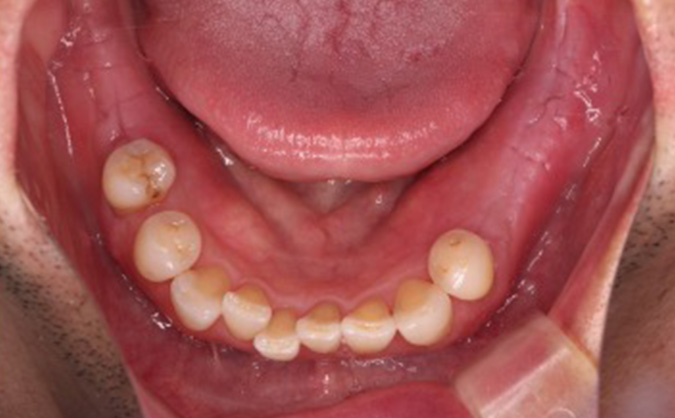

症例05

治療前

治療後

主訴 咬めるようになりたい

見た目をきれいにしたい

治療期間 9ヶ月

治療費 ¥1,640,000(※インプラントのみ)

治療内容 左下大臼歯2本、右下大臼歯2本

インプラント埋入

上前歯セラミック矯正

治療のリスク 術後疼痛 患部腫脹

主訴

咬めるようになりたい

治療期間

9ヶ月

治療費

¥1,640,000(※インプラントのみ)

治療内容

左下大臼歯2本、右下大臼歯2本

治療のリスク

術後疼痛 患部腫脹